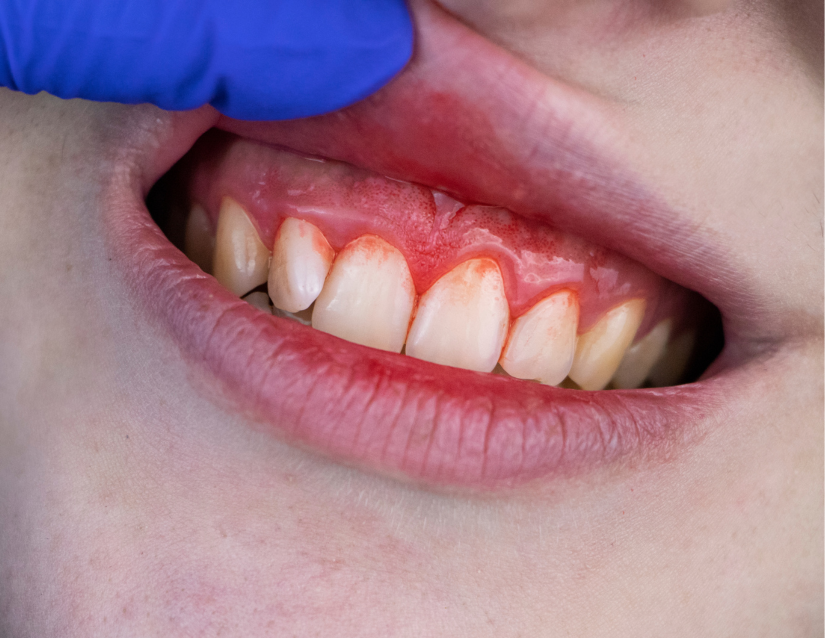

Gingivitis

La gingivitis se caracteriza por la inflamación y el enrojecimiento de las encías, causados por la acumulación de placa bacteriana.